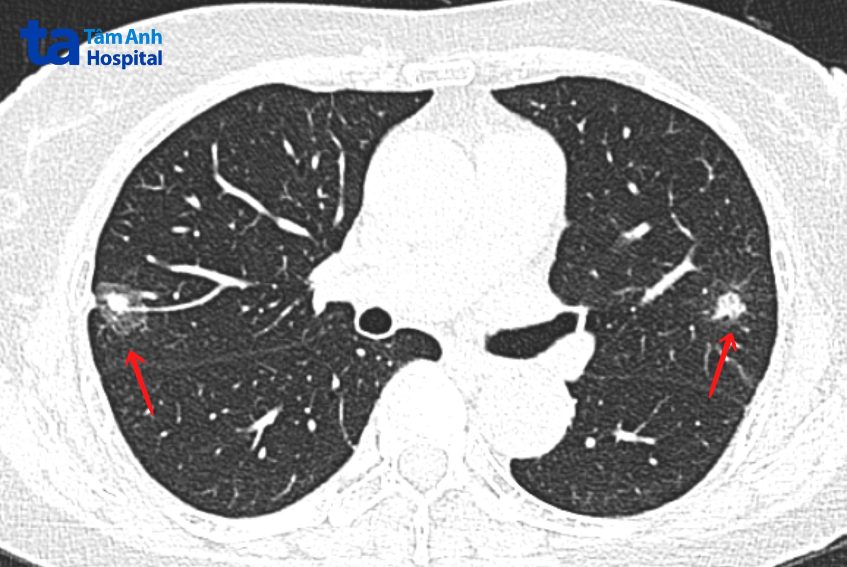

Bà Duyên không có dấu hiệu bất thường, đến Bệnh viện Đa khoa Tâm Anh Hà Nội khám sức khỏe phát hiện hai khối u kích thước 16×16 mm và 27×28 mm ở hai bên phổi. Tiến sĩ, bác sĩ Vũ Hữu Khiêm, Trưởng khoa Ung bướu, chẩn đoán bà Duyên ung thư phổi nguyên phát đa ổ ở giai đoạn sớm, có thể phẫu thuật điều trị triệt căn.